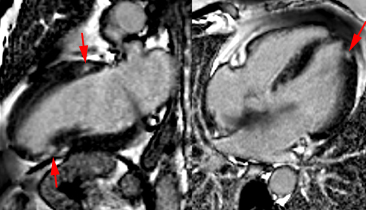

Récidive de rhadomyosarcome de la valve mitrale 6 mois apres resection tumorale et remplacement valvulaire mitral par une prothèse mécanique. Trois petites lésions punctiformes suspectes de métastases sont mises en évidence sur l’imagerie T1 post-gadolinium (flèches).

Récidive de rhadomyosarcome de la valve mitrale 6 mois apres resection tumorale et remplacement valvulaire mitral par une prothèse mécanique. Trois petites lésions punctiformes suspectes de métastases sont mises en évidence sur l’imagerie T1 post-gadolinium (flèches).